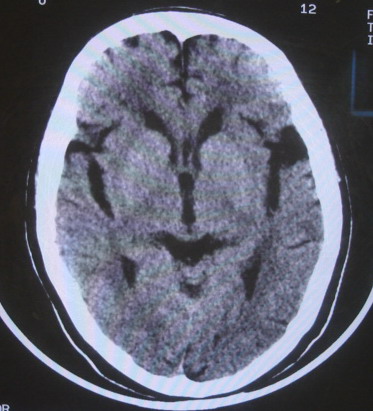

女  67岁 双下肢无力,行动不灵便

脑萎缩,腔隙性脑梗塞.

右顶叶腔梗

双侧额桥束及左侧脑室旁多发腔梗塞+老年性脑改变

多发腔梗、老年性脑改变、脑白质异常。